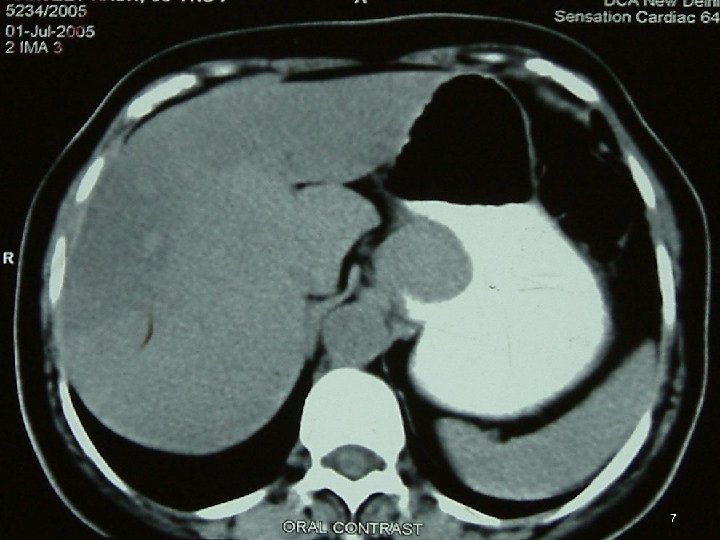

Investigations • • • Chest X Ray USG CECT EUS Ba Swallow 3

Diagnosis • FDG PET = mandatory ►FDG-PET CT scan is ideal • MD-CE-CT = image modality of choice for abdomen (if FDG-PET-CT is not available) • MR • Evaluate by Chol or RECIST criterion 46

Diagnosis • Polyp / Metastases of Lobular Breast CA in Ut • GIST, Lymphoma / 2 nd primary at GI jn